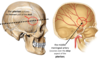

What is the pterion and why is it significant ?

It is the thinnest part of the skull formed between the Frontal, parietal, temporal and sphenoid bones

The middle meningeal artery courses deep to it ==> it is at risk to damage

Label the arteries indicated

Note that the external carotid arteries remain external to the cranium and supply the face, scalp and neck

Label the indicated structures